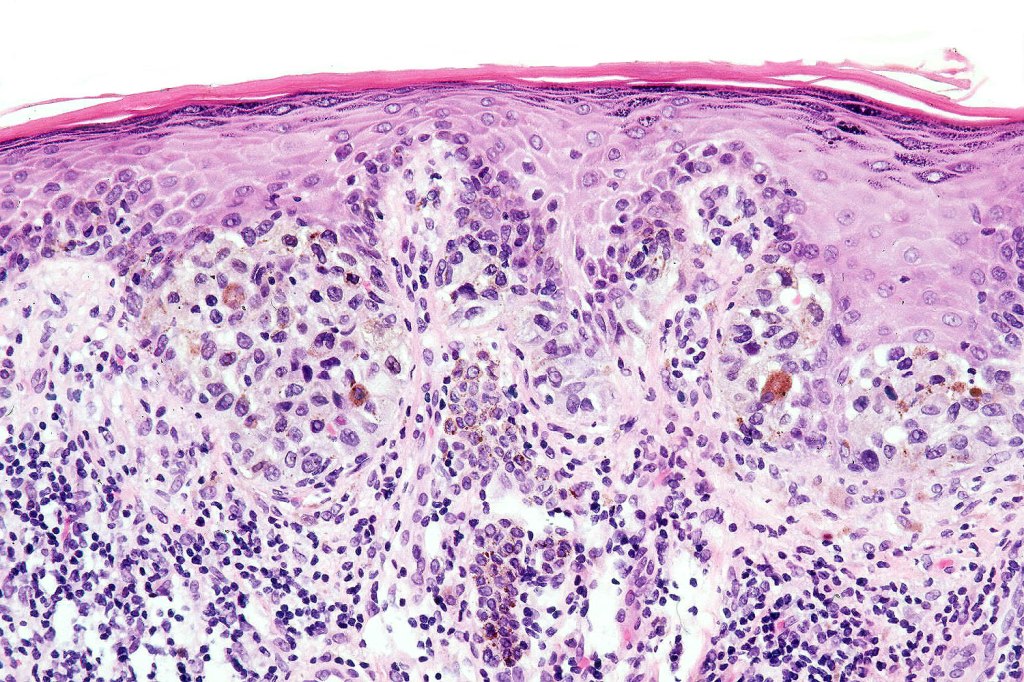

Histological features

•Junctional/compound

•Large dyscohesive nests with retraction artifact, not restricted to the tips of the epidermal ridges

•Bridging common, often over multiple rete ridges

•Variable atypia (can be marked)

•Central pagetoid spread

•Superficial dermal atypia